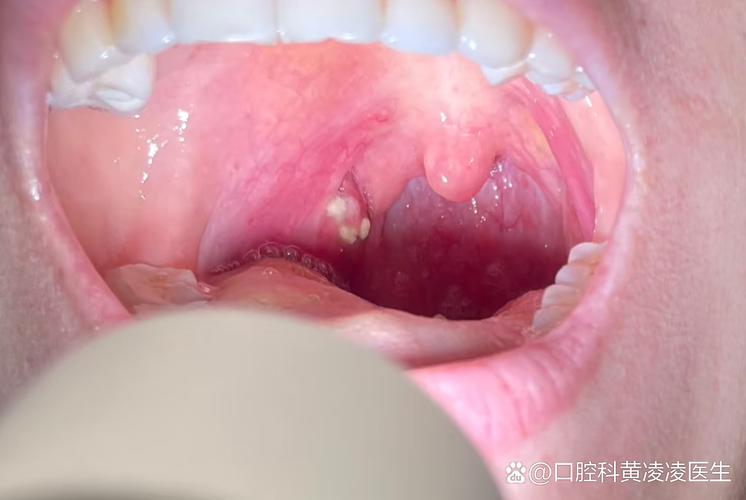

口腔有白点是什么病啊

下面我将口腔白点可能的原因分为几大类,从最常见到需要警惕的情况进行说明:

口腔念珠菌病 (俗称“鹅口疮”)

- 症状:口腔黏膜(如舌头、内颊、上颚)出现乳白色、豆腐渣样的斑块,不易擦去,强行剥离后下方会发红、出血,严重时可能伴有口干、烧灼感或味觉改变。

- 原因:由白色念珠菌(一种真菌)过度增殖引起,常见于婴幼儿、老年人、免疫力低下者(如糖尿病患者、HIV感染者、长期使用抗生素或激素者)。

- 处理:需要抗真菌药物治疗,如制霉菌素、氟康唑等,同时要增强免疫力,保持口腔干燥清洁。

口腔黏膜扁平苔藓

- 症状:一种慢性炎症性疾病,表现为口腔黏膜上出现白色、灰白色的条纹、网状或斑块状病损,有时可伴有糜烂和疼痛,病损两侧常有对称性。

需要高度警惕的疾病(癌前病变或癌症)

口腔白斑

- 症状:口腔黏膜上出现不能被擦除的白色或灰白色的斑块,质地较硬,表面可有皲裂或溃疡,通常没有明显的疼痛感,这是最危险的一点,容易被忽视。

- 处理:这是最重要的! 口腔白斑被视为癌前病变,有一定的癌变风险,一旦发现,必须立即就医,医生会根据情况进行评估,可能需要定期复查或手术切除活检,以防癌变。

口腔鳞状细胞癌

- 症状:早期可能表现为无法愈合的溃疡、硬结或肿块、白色或红色的斑块,随着发展,可能出现疼痛、出血、牙齿松动、张口受限、颈部淋巴结肿大等症状。